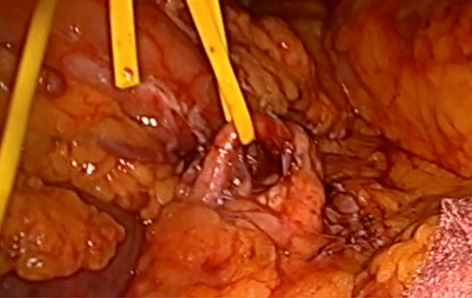

Until now there have been early attempts at producing advanced laparoscopic systems but these have been cumbersome and limited in their engineering. We present a revolutionary new advanced laparoscopic instrumentation system called ArtiSential. The ArtiSential instruments include bipolar forceps, Maryland dissector, monopolar spatula, monopolar hook, needle holder, with more on the way. They allow a wide range of articulating movement through 7 degrees of freedom that can mimic the dexterity of robotic platforms (Fig. 1). Traditional laparoscopic instruments have limited range of movements but these instruments allow for complex articulating movements in different planes which can be further exploited around the fulcrum of the port. This additional articulation means that there is better access to difficult part of anatomy. Furthermore, there is tactile feedback on the instrument handset which is lightweight and disposable.

Our initial series of cases include pelvic colorectal surgery and demonstrate the advantages of articulating instruments (Fig. 2). Further, we demonstrate that there is a learning curve to these instruments to maximise their benefit during complex procedures. We suggest adopting the formal training programme which includes a period of dry lab training before embarking on clinical cases so that surgeons may truly benefit from these advanced instruments. This also allows for safer introduction of new technology.

Advanced laparoscopic instruments such as ArtiSential should be used to make challenging aspects of laparoscopic surgery more accessible. These are not substitute for all straight instruments but best used to maintain precision during difficult manoeuvres in combination with traditional instruments.